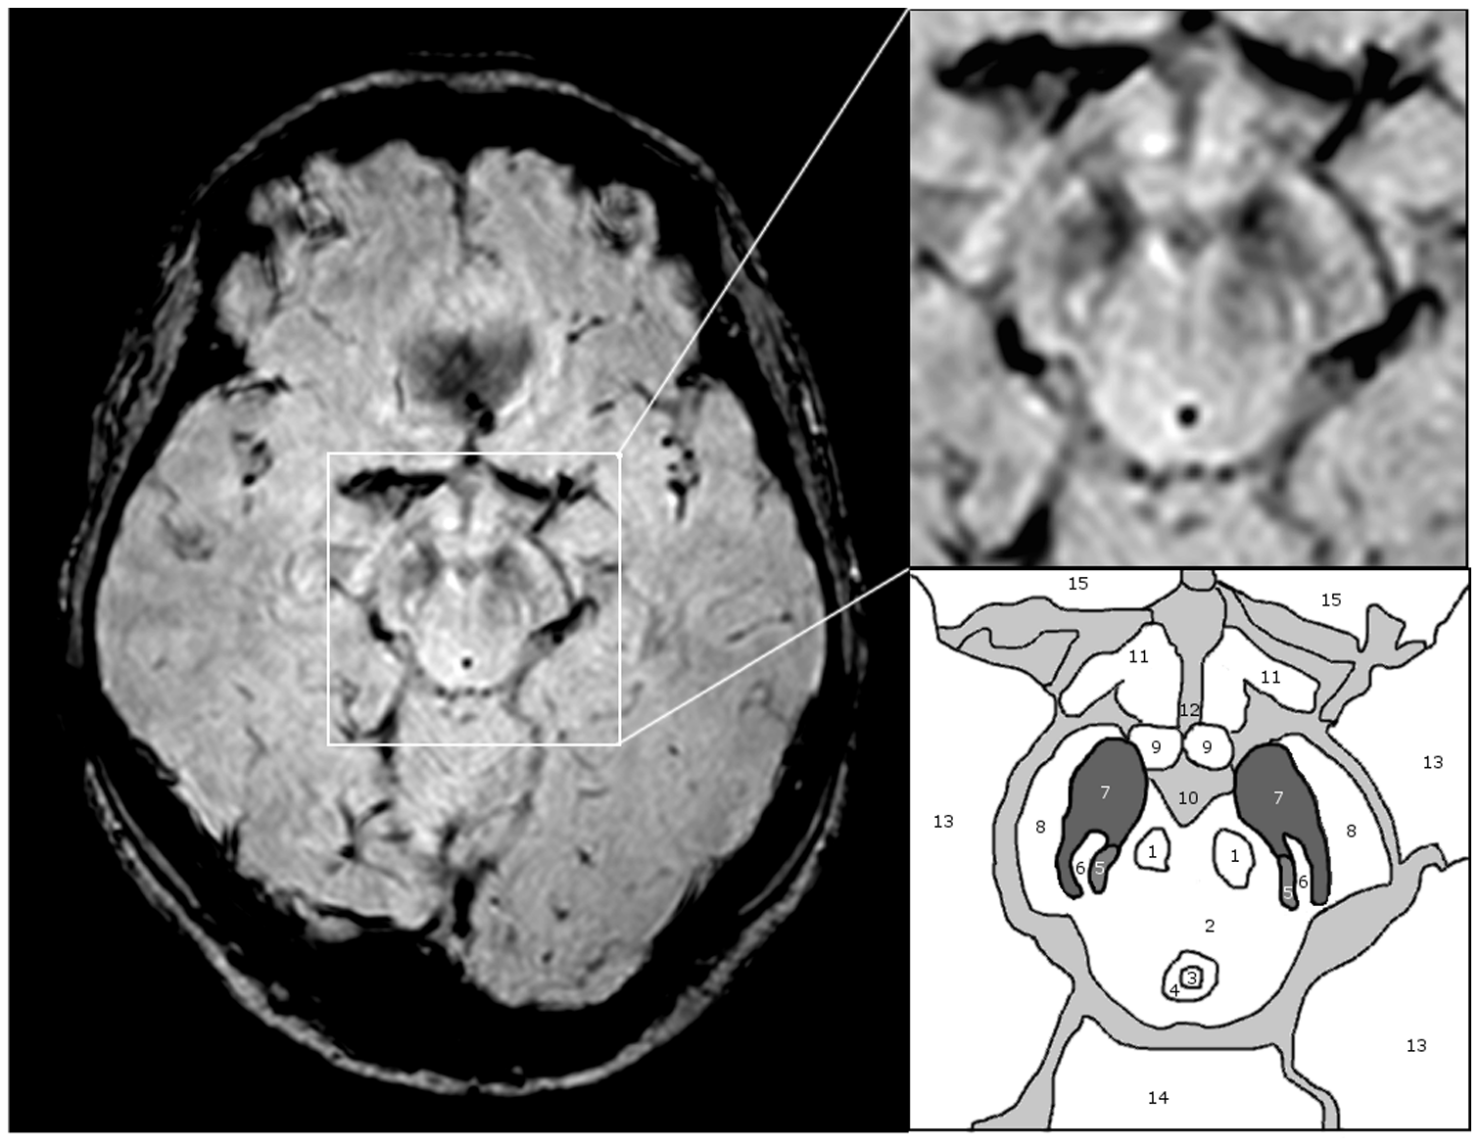

Sídlo vědomí není v neokortexu? Starobylé části mozku jsou klíčem k naší mysli, naznačuje věda

Dlouho se mělo za to, že lidské vědomí sídlí hlavně v neokortexu – evolučně nejnovější části mozku, která zajišťuje řeč, logiku a plánování. Nové studie v oblasti neuropsychologie však ukazují, že klíčovou roli mohou hrát i jeho nejstarší struktury: subkortex a mozeček.